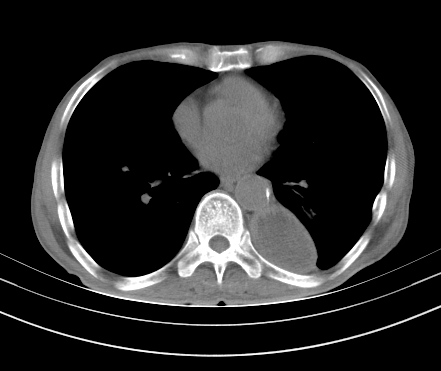

以下是引用gaoshengjiang在2008-5-30 19:53:00的发言:[br]右上叶可见大片实变影,其内可见充气支气管影及囊状影,右上叶尖端支气管走形区可见结节样影,左侧胸腔内可见胸腔胃影。纵隔淋巴结肿大。[br]考虑:1.右上肺阻塞性肺炎伴肺脓肿形成。支持转移所致。[br] 2.左侧胸腔胃。